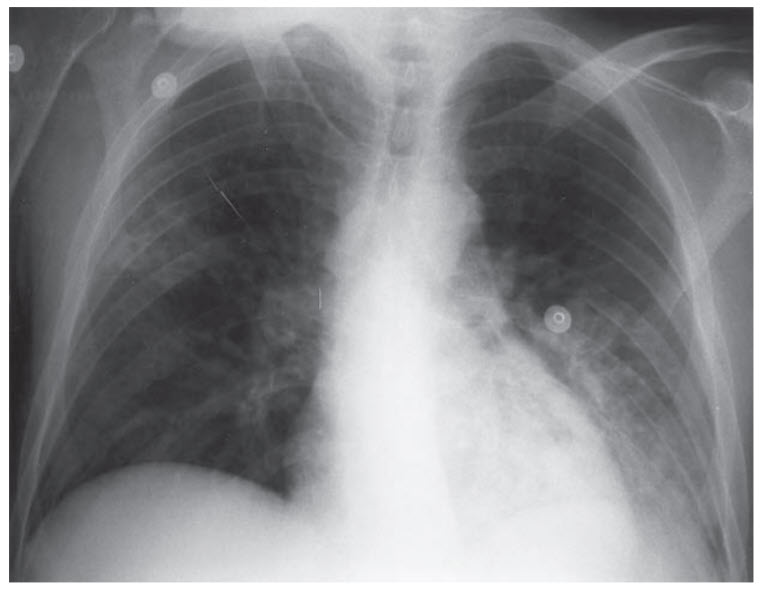

A 35-year-old man presents with increasing dyspnea and a nonproductive cough over the last week. Vital signs show a temperature of 38.6°C, blood pressure of 110/82 mmHg, heart rate of 112 beats per minute, and an oxygen saturation of 91%. He has a history of HIV infection and is currently not taking any medications. A chest x-ray is performed (Figure below), and his laboratory values are shown below.

The patient has a CD4 count of 13/mm3 and a calculated A–a gradient of 47.

Trimethoprim–sulfamethoxazole with prednisone. Trimethoprim–sulfamethoxazole is the treatment for PCP pneumonia, which occurs in immunocompromised patients (especially HIV positive patients with a CD4 count <200). The history, chest x-ray, and elevated lactate are all consistent with PCP pneumonia. (E) When the PaO2 is <70 mmHg or the A–a gradient is >35, prednisone should be given before antibiotics to limit the amount of pulmonary inflammation in response to PCP cell death and lysis. (B) HIV treatment with tenofovir/emtricitabine and raltegravir should not be initiated immediately since immune reconstitution may lead to worsening inflammation and respiratory distress. (C) This patient does not have findings that suggest TB infection. (D) Vancomycin and piperacillin/tazobactam is a broad-spectrum empiric antibiotic regimen; however, the likely diagnosis is PCP pneumonia and thus antibiotics should be tailored to this organism.